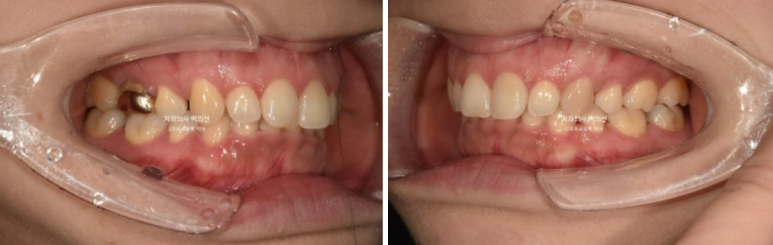

24.03

과개교합이 심하면 위 앞니 뒤에 철사유지장치를 붙일 수 없습니다. 아랫니에 씹혀 불편하고 또 철사가 금방 떨어집니다.

송곳니 뒤쪽 2mm정도의 벌어진 공간이 보입니다.

10년 전 외국에서 교정할 때 발치한 첫번째 작은어금니가 있었던 공간이고, 재발로 인해 공간이 다시 벌어졌습니다.

이분처럼 과개교합이 남은채로 교정이 마무리 되면 철사유지장치를 붙일 수 없으며 이는 곧 재발로 이어집니다. 철사유지장치가 잘 붙어있었다면 발치공간이 2mm씩이나 벌어지진 않았을 것 입니다. 교정 마무리 단계에서 과개교합만큼은 반드시 끝장을 봐야 하는 이유입니다.